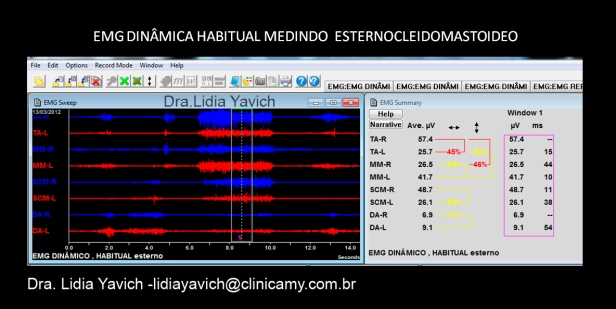

A eletromiografia de superfície dinâmica mostra importante assimetria dos temporais superficiais direito e esquerdo, e baixa atividade de ambos os masseteres. Os trapézios não mostram atividade durante o fechamento mandibular, o que é fisiologicamente correto. Importante atividade dos digástricos em fechamento, o que é fisiologicamente incorreto.

A eletromiografia de superfície dinâmica mostra importante assimetria dos temporais superficiais direito e esquerdo, e baixa atividade de ambos os masseteres. Os esternocleidomastoideo mostram atividade durante o fechamento mandibular, o que é fisiologicamente incorreto ( o esternocleidomastoideo não é um músculo da mastigação). Importante atividade dos digástricos em fechamento, o que é fisiologicamente incorreto.